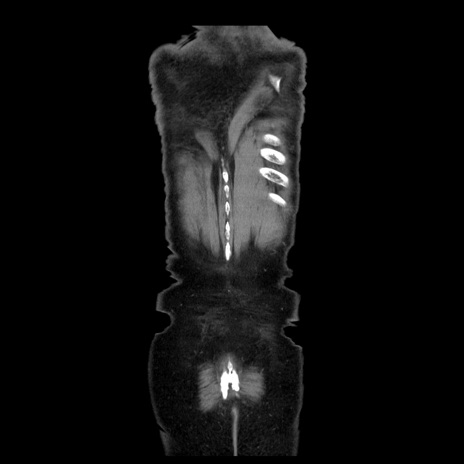

横断像

【症例】70歳代男性

【現病歴】肝硬変・肝細胞癌にてかかりつけの方。約9時間前に食後より腹痛出現。症状が徐々に増悪し、嘔吐出現したため来院。

【既往歴】肝硬変、肝細胞癌(RFA、TACE後)